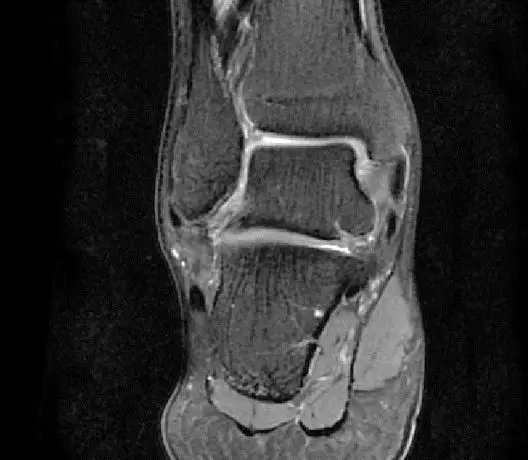

此片可以看到韧带结构消失,T2相高信号,整体韧带增粗,松弛,腓骨肌腱内侧,跟绯肌腱的形态完全消失,它的韧带也是松弛增粗的。所以考虑是踝关节距腓前韧带的损伤。